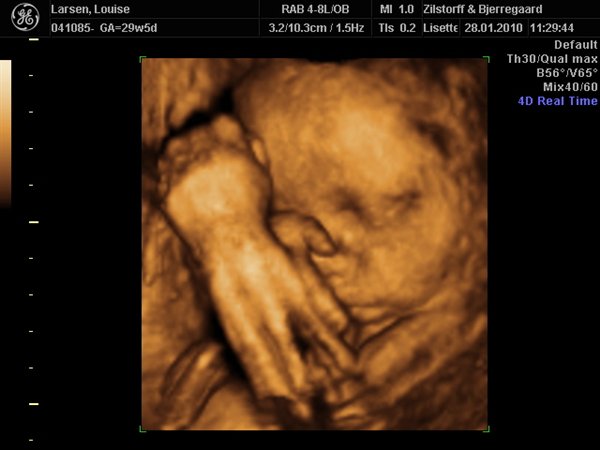

Vi har været til 3D/4D Scanning idag. Og sikke en vild oplevelse.... Har aldrig (udover min fødsel af Nicklas) prøvet noget så stort!

Her er lidt billeder: